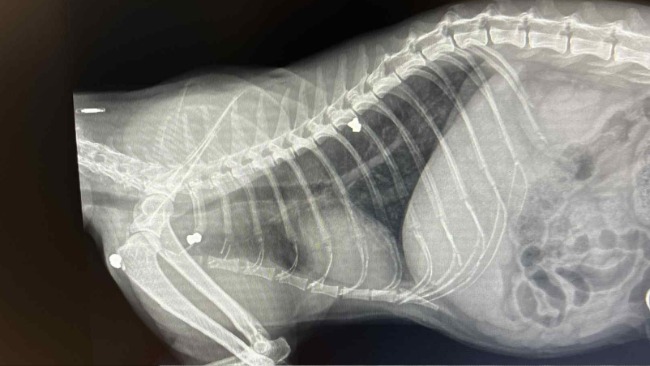

Trzy metalowe śruty tkwią w ciele Draco. Trzy metalowe dowody na to, że ktoś uznał, że jego życie jest nic nie warte... Że cierpienie to zabawa.

Jego ciało to mapa cierpienia. Kolejne badania ukazują kolejne przykre diagnozy. Pozytywny test na FIV. Wirus nabytego niedoboru immunologicznego kotów, osłabia jego organizm i sprawia, że każda infekcja to poważne zagrożenie.